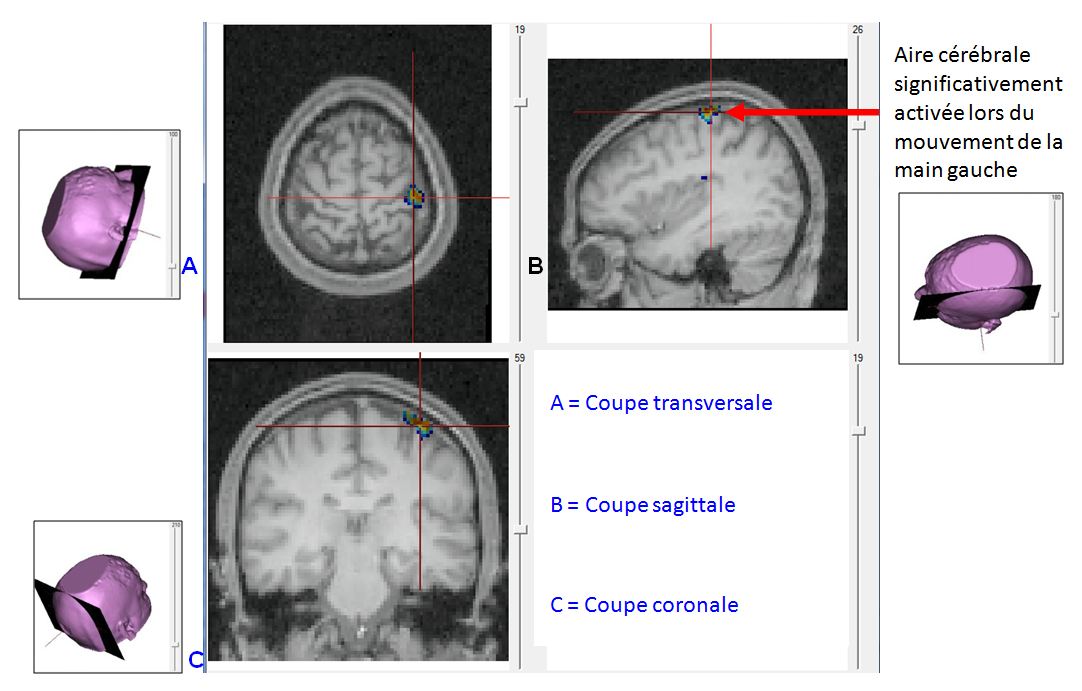

Production bouger main gauche.JPG